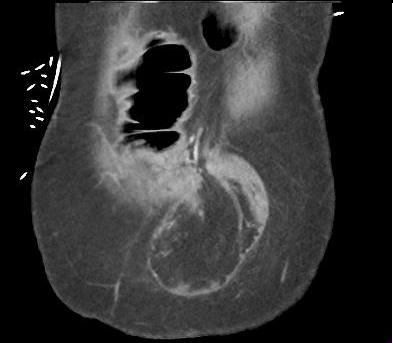

Occlusion du colon a cause

cancer du colon droit . Colon ascedante en amont de

lesion est tres dilate avec imcompetence de la

valvule Bauhin ( fleche jaunne ) .La masse du tumeur

est hyper-dense a bord irregulier (fleche rouge )

situe au colon pres de angle colique droite .

Le colon en aval est collapse . |

|

Meme cas en coupe axiale .

La masse du tumeur est hyper-dense a bord irregulier

( fleche rouge ) situe a la region sous hepatique

droit |